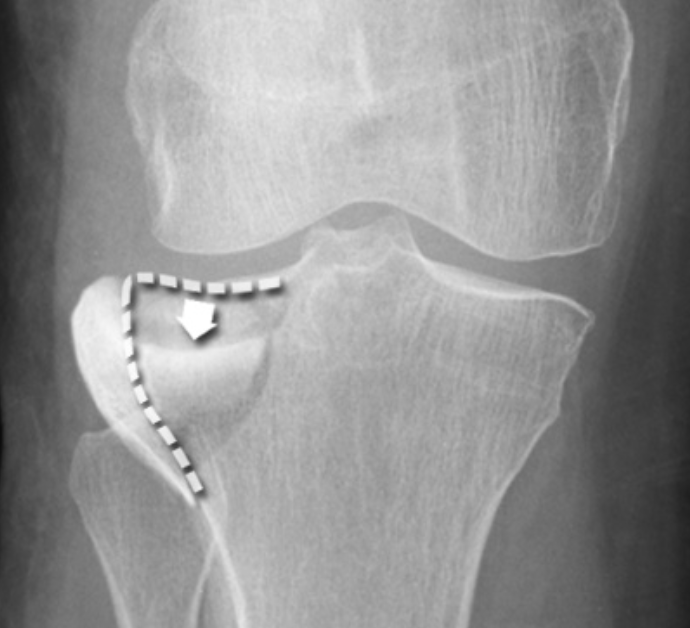

Describe the fracture seen in this X-ray [1]

Lateral tibial plateau fracture

* The fracture fragment is displaced and depressed from its normal position (dotted line)